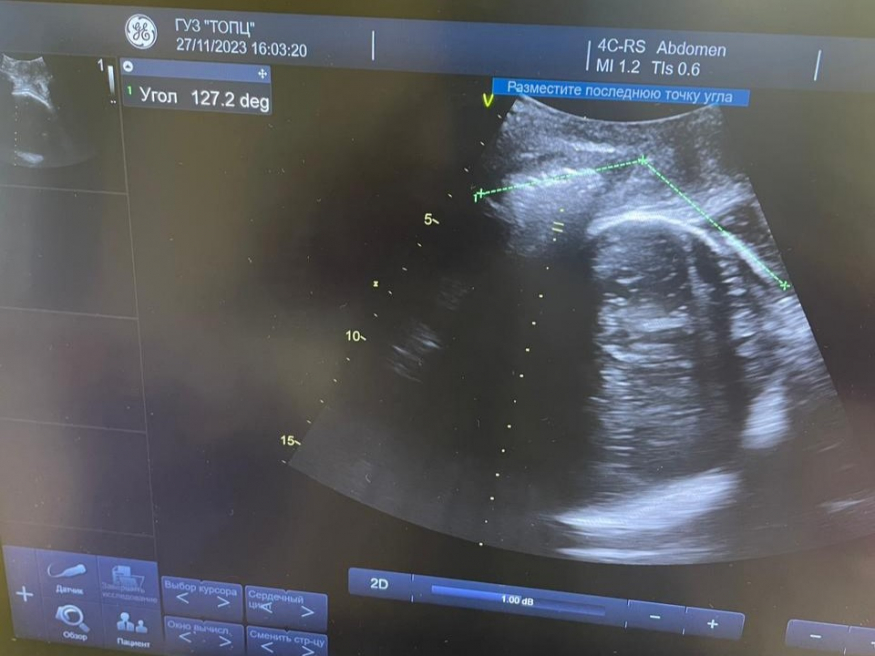

В Тульском областном перинатальном центре применяют новый метод ведения родов — ультразвуковую диагностику течения родов.

В  режиме реального времени врачи могут точно определить положение головки плода и  ее продвижение в  потужном периоде родов, до  этого точность определения головки плода в  области малого таза варьировалась между 50–60%.

«Уже проведено более 20 родов с  использованием ультразвуковой диагностики. Применение этого метода позволяет своевременно решать вопрос об  оперативном родоразрешении и  избежать лишних оперативных вмешательств», — рассказал заместитель главного врача по  акушерству и  гинекологии Петр Мартыненко.

Фото:  Тульский областной перинатальный центр